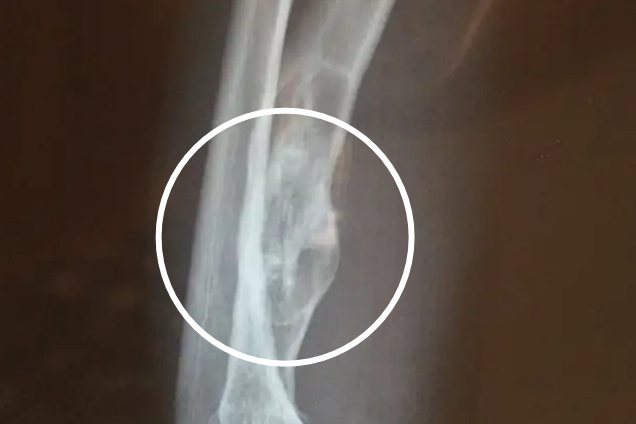

骨囊肿好发于儿童和青少年的长管状骨干骺端。骨囊肿生长于髓内,一般是边界清楚的无痛性的圆形肿物,肿物含有囊腔,腔内含有清亮液体。骨囊肿早期体积较小,大部分患者不伴有明显症状,一般难以察觉。部分患者早期便会出现轻微疼痛,且劳累后会出现酸胀感觉,但症状不明显,因此容易被忽视。若是骨囊肿早期体积较大,肢体还可以出现轻微肿大。

部分骨囊肿患者可以自愈,尤其是在骨囊肿部位发生骨折后,囊内可以被新生骨填充。临床上对于骨囊肿治疗主要包括病灶刮除、自体或异体骨移植填充以及甲泼尼龙注射疗法等。若是肢体出现不明原因的肿大,伴有不适感觉,应该及时就医诊治。